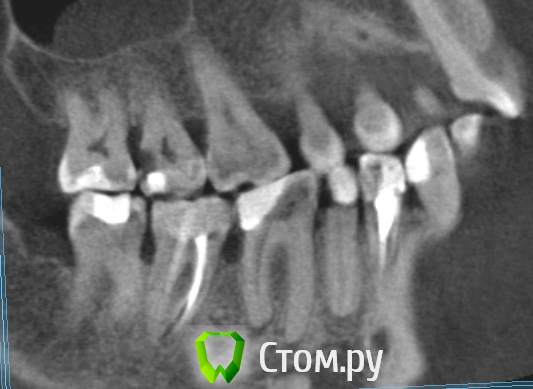

Dmitrich Опубликовано 30 сентября, 2014 Поделиться Опубликовано 30 сентября, 2014 Здравствуйте уважаемые форумчане. Вообщем такая у меня проблема, постараюсь описать менее сумбурно. Сначала я удалил 4.7 зуб из за кариеса корня. После этого примерно через неделю начались боли с другой стороны челюсти. Пришел на прием - мне по рентгену опредилили больной 3.7 (там был глубокий кариес и раза 3 переставляли пломбу на протяжении лет так 20) Его депульпировали, но боль не прошла. Сначала болело при накусывании (это нормально как я понимаю), потом просто стали ноющие боли. На месяц я уехал из города и боли были разной интенсивности. Обращался к двум разным стоматологам в отъезде - все гвоорили что это отстаточное явление после лечения. Постукивание по зубу чувствительно до сих пор. С тех пор уже 3 месяца - ноющие боли не проходят. Обращался в разные клиники, делал КТ месяц назад. Может не болеть дня 3-4 совсем, я уже обрадуюсь, на следующий день опять начинает тянуть. Утром всегда не болит, к обеду начинает. Чистили карман между 6 и 7. Результат улучшается на день-два. Ходил на прием к ортодонту, тот сказал нужно лечить 6й, состояние десен почти в норме, ко крайней мере острого воспаления нет. С КТ сделал скриншоты 6го и 7го, прикладываю. 6й зуб проверяли проводимость нерва аппаратом - результат ок )) Что мне все таки делать в данной ситуации? В клинике где лечил зуб говорят он вылечен нормально. Ссылка на комментарий

M@estro Опубликовано 30 сентября, 2014 Поделиться Опубликовано 30 сентября, 2014 Проблема в 3.6 Ссылка на комментарий

Korel Опубликовано 30 сентября, 2014 Поделиться Опубликовано 30 сентября, 2014 Проблема в 3.6 И (или) в 35 Ссылка на комментарий

Паращук Роман Опубликовано 30 сентября, 2014 Поделиться Опубликовано 30 сентября, 2014 (изменено) Или 3.6,2.7. Возможна трещина в 3.7 Изменено 30 сентября, 2014 пользователем Паращук Роман Ссылка на комментарий

Dmitrich Опубликовано 30 сентября, 2014 Автор Поделиться Опубликовано 30 сентября, 2014 Спасибо всем за советы. 2.7 сделал с месяц назад, не помогло. 3.6 получается делать точно? Странно вроде относительно недавно (года 2 назад) менял там пломбу из за того, что откололся край - вообще никаких проблем не было. Нерв проверяли - жив. То что на верхушках корня там - три месяца назад было тоже самое. А вот с трещиной вы напугали. Смотрели эту КТ несколько раз несколько стоматологов, трещину никто не увидел. Она же вроде сильно должна болеть? Ссылка на комментарий